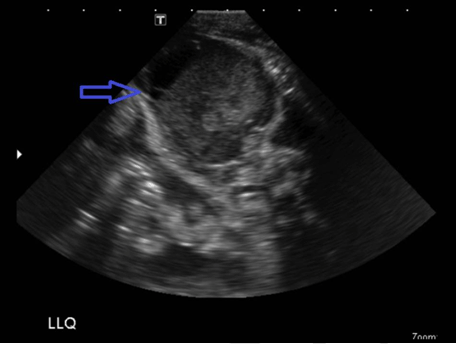

A 36-week-gestational age female was delivered urgently via cesarean section due to developing intra-abdominal fluid and bowel distention on ultrasound in utero. The mother was a 27-year-old G2P1001 Caucasian otherwise healthy female. Apgar scores post cesarean section was six and nine at one and five minutes respectively. On delivery, the patient required transfusion secondary to anemia (20% hematocrit with normal range being 55–68%). Paucity of gas in the left hemiabdomen was noted on plain films. Ultrasound demonstrated a heterogeneous mass in the left abdomen medial to the spleen and anterior to the left kidney measuring approximately 4.8x3.6x4.9 cm (Figure 1) (Figure 2) (Figure 3). This mass lacked flow on Doppler (Figure 4). Ultrasound also was notable for moderate complex ascites with debris consistent with blood products (Figure 2). Computed tomography scan confirmed the presence a large unilocular well circumscribed mass adjacent to the left colon with smooth margins and associated extensive complex ascites (Figure 5) (Figure 6). Our differential diagnosis was a complicated mesenteric cyst versus hemorrhagic ruptured ovarian cyst.

Figure 2: Left lower quadrant heterogeneous mass (orange arrow). Ascites with simple (red arrow) and complex (blue arrow) components.

Figure 3: Ultrasound of left lower quadrant showed a heterogeneous mass in the left abdomen medial to the spleen and anterior to the left kidney measuring approximately 4.8x3.6x4.9 cm.